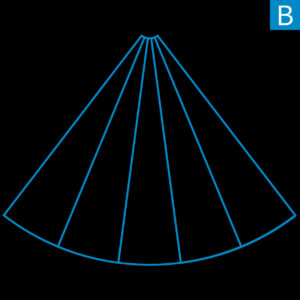

ZONE Sonography Technology (ZST) is a revolutionary, software-driven approach to acoustic data acquisition and image formation that breaks the barriers of conventional ultrasound imaging. Using a variable number of large imaging “ZONES”, ZST is capable of utilizing up to 90% more ultrasound data than conventional ultrasound imaging platforms and at speeds 10 times faster. This expanded acoustic data set is retained and processed by patented high-speed digital processing techniques and software algorithms that are radically different from slow and cumbersome hardware-based imaging methods.